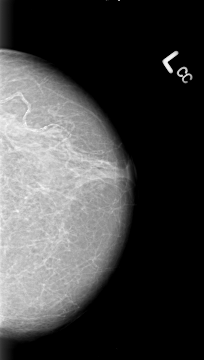

B_3013_1.LEFT_CC

LEFT_CC LINES 4312 PIXELS_PER_LINE 2440 BITS_PER_PIXEL 12 RESOLUTION 50 NON_OVERLAY

FILE: B_3013_1.RIGHT_CC.OVERLAY

TOTAL_ABNORMALITIES 2

ABNORMALITY 2

LESION_TYPE MASS SHAPE IRREGULAR-ARCHITECTURAL_DISTORTION MARGINS SPICULATED

ASSESSMENT 5

SUBTLETY 5

PATHOLOGY MALIGNANT

TOTAL_OUTLINES 1

BOUNDARY